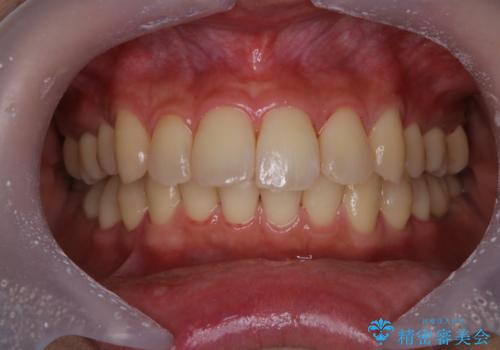

- 見た目をきれいにしたいとのことで来院されました。PMTC60分コースを行いました。

また、PMTCを行うことで、ステインやバイオフィルムが除去され、ご自身本来の歯の色となります。

- 歯を白くする目的の施術ではありません